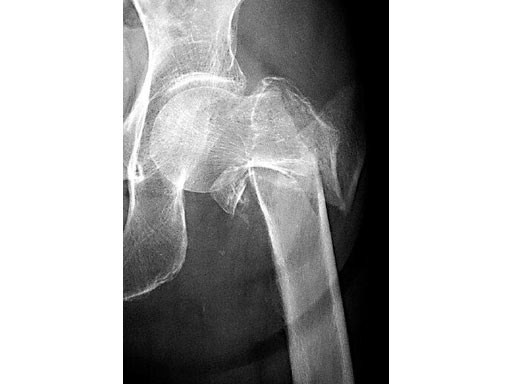

The Locking Trochanter Stabilization Plate is intended for the treatment of unstable pertrochanteric fractures in combination with the Dynamic Hip Screw (DHS), especially for 4-part fractures with greater trochanter.

79-year-old woman.